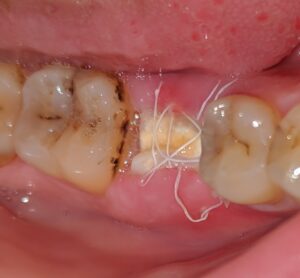

پس از کشیدن دندان یا جراحی دهان

یکی از شایعترین دلایل، بعد از کشیدن دندان است که اگر لخته خون درست تشکیل نشود یا تکهای از ریشه باقی بمواند، استخوان فک نمایان میشود، گاهی هم تحلیل استخوان فک (resorption) باعث میشود لثه عقب رفتگی داشته باشد و استخوان بیرون روی کند.

یک بیمار 45 ساله داشتیم که بعد از کشیدن دندان آسیاب، استخوانش بیرون زده بود چون عفونت کوچکی وجود داشت، درمانش با برداشتن تکه باقی مانده و آنتیبیوتیک حل شد. مطالعات نشان میدهد که در 10 تا 20 درصد موارد کشیدن دندان، اگر مراقبت درست صورت نگیرد، این مشکل پیش میآید.